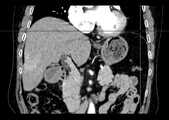

Fig. 8c is a schematic view of a sequence of CT images viewed from the coronal direction.

fig. 8a-8c are raw three-dimensional data of sequential CT images viewed from three directions, the transverse, sagittal and coronal planes, respectively. Fig. 9a to 9c are the second binarized images obtained after the method removes the bed plate area, respectively, and it can be seen from fig. 9a to 9c that none of the skin surface contours of the human body area is damaged. Fig. 10a to 10c are respectively third binarized images obtained after filling the cavity by the method, and it can be seen from fig. 10a to 10c that the third binarized images are completely overlapped with the original three-dimensional data of the sequence CT image, and the lung region with a low threshold value is effectively filled. As can be seen from FIGS. 11a-11d, after another serial CT image is reconstructed by the method, the three-dimensional model of the skin can be fused with the third binary image and the serial CT image. And finally mapping the obtained three-dimensional model of the skin back to a 2D mode, and comparing the coincidence degree of the skin boundary in the three-dimensional model of the skin and the binary image to obtain figures 12a-12 c. In addition, the three-dimensional models of the skin of other parts of the human body obtained by the method are shown in figures 13a-13 c.